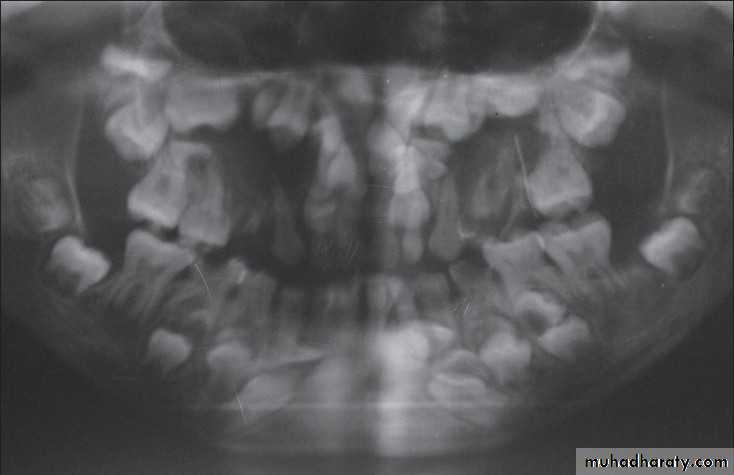

Influence of Premature loss of Primary Teeth on Eruption time of their Successors:

Primary molars loss at 4 or 5 years leads to delay eruption of premolars.

Extraction of the primary molars occurs after the age of 5 years, there will be a decrease in the delay of premolar eruption.

Variations in the Sequence of Eruption:

Sequence of eruption of primary dentition:Sequence of eruption of permanent dentition:

ABDCEABDCE

6124537861234578